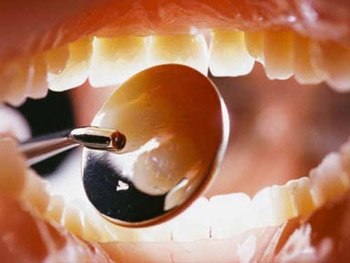

Судебно-стоматологическая экспертиза повреждений зубов

Повреждения зубов составляют 0,9--3S&% среди челюстно-лицевой травмы, или 0,2% среди судебно-медицинских экспертиз, проводимых по поводу телесных повреждений у живых лиц. Чаще всего повреждения зубов возникают от действия тупых твердых предметов вследствие удара по лицу в область зубных рядов или при падении лицом вниз. Возможна травма зубов при резком смыкании челюстей от удара по верхней части головы. Травма зубов наблюдается при переломах челюстей. Она может иметь место при врачебных ...